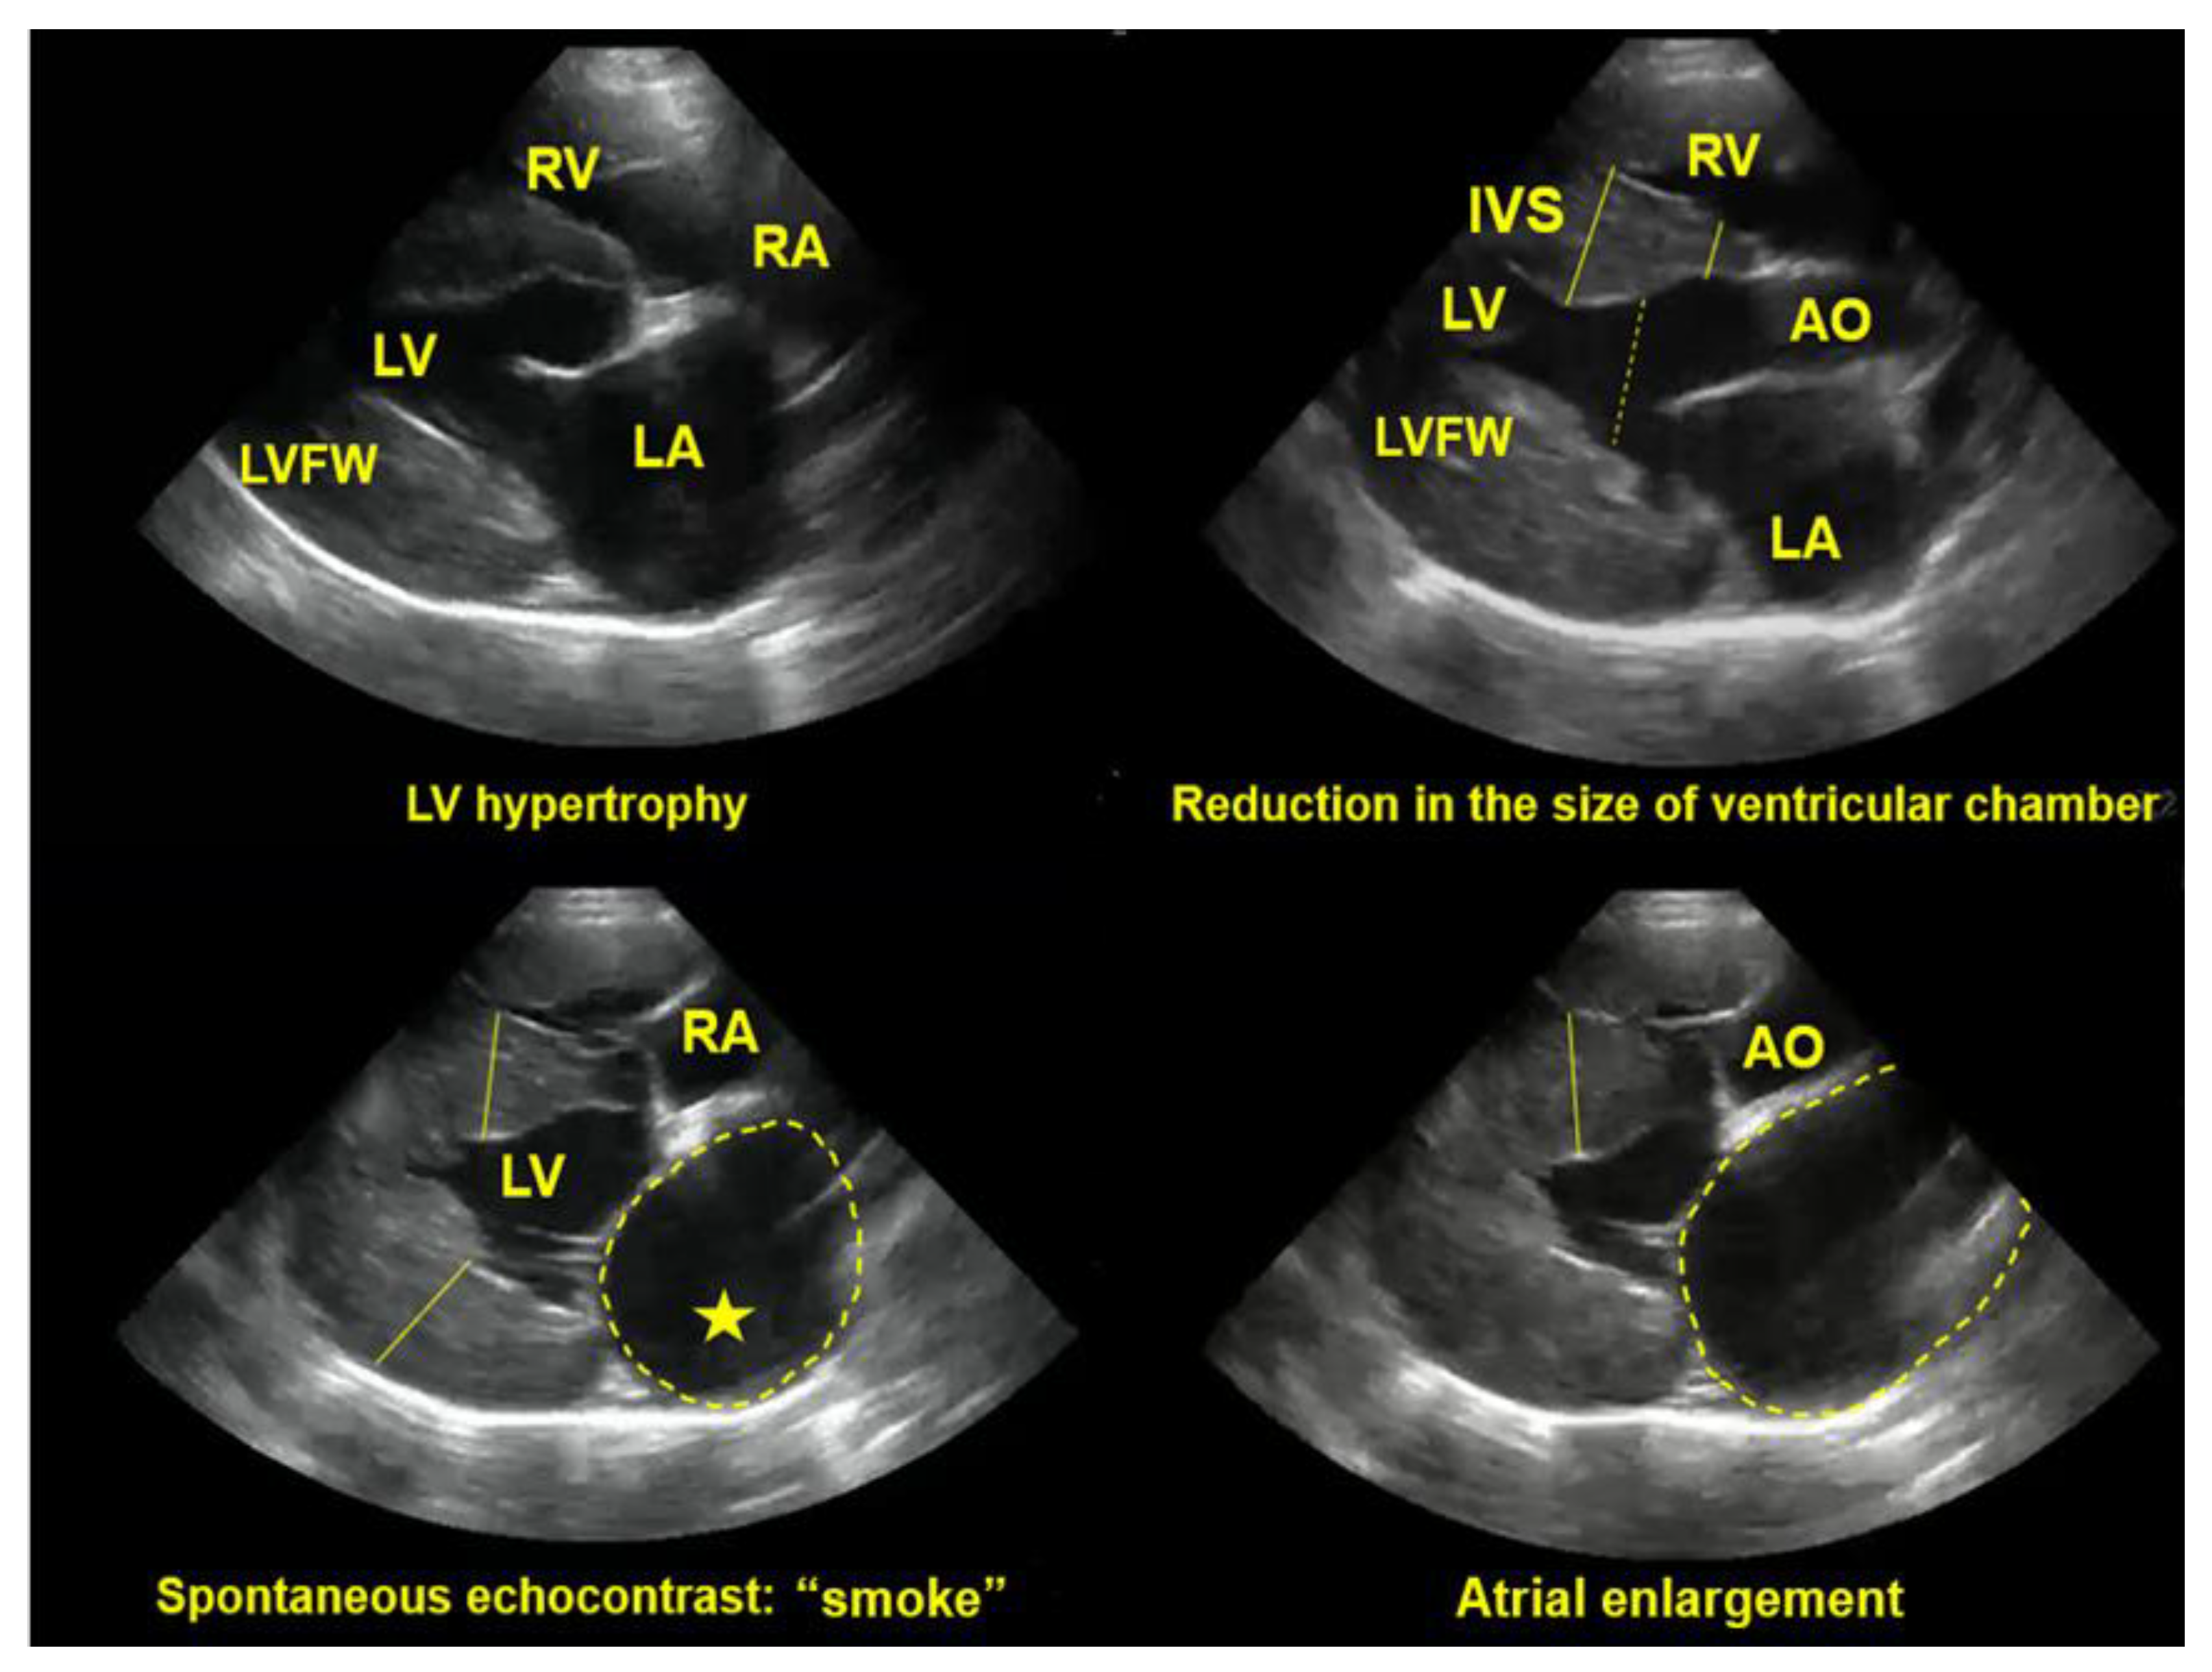

- Abbott, J.A.; MacLean, H.N. Two-Dimensional Echocardiographic Assessment of the Feline Left Atrium. J. Vet. Intern. Med. 2006, 20, 111–119. [Google Scholar] [CrossRef] [PubMed]

- Maerz, I.; Schober, K.; Oechtering, G. Echocardiographic measurement of left atrial dimension in healthy cats and cats with left ventricular hypertrophy. Tieraerztl. Prax. Ausg. K. Kleintiere. Heimtiere. 2006, 34, 331. [Google Scholar]

- Schober, K.E.; Maerz, I. Assessment of left atrial appendage flow velocity and its relation to spontaneous echocardiographic contrast in 89 cats with myocardial disease. J. Vet. Intern. Med. 2006, 20, 120–130. [Google Scholar] [CrossRef]

- Colakoglu, E.; Sevim, K.; Kaya, U. Short communication Assessment of left atrial size, left atrial volume and left ventricular function, and its relation to spontaneous echocardiographic contrast in cats with hypertrophic cardiomyopathy: A preliminary study. Pol. J. Vet. Sci, 2024, 27, 487–490. [Google Scholar] [CrossRef] [PubMed]

- Schober, K.E.; Chetboul, V. Echocardiographic evaluation of left ventricular diastolic function in cats: Hemodynamic determinants and pattern recognition. J. Vet. Cardiol. 2015, 17, S102–33. [Google Scholar] [CrossRef] [PubMed]